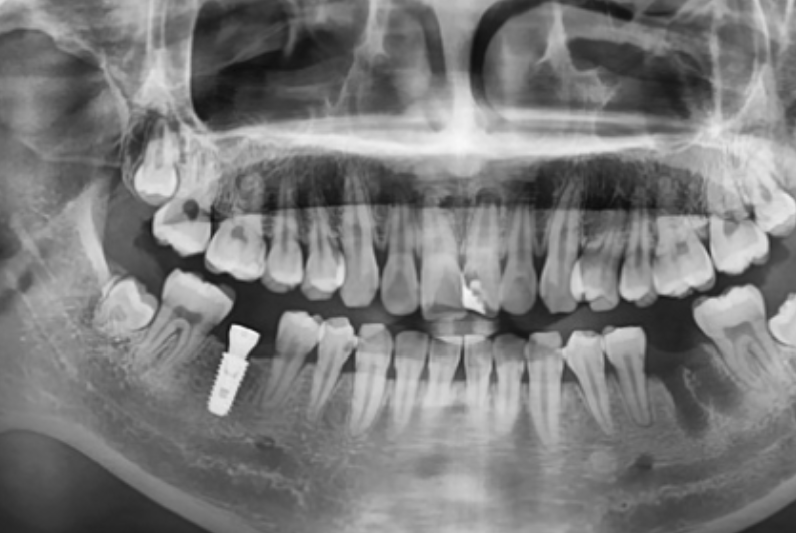

< Some implant surgery cases >

Treatment period: 23.12.25 - 24.6.28

Problem tooth location: Maxillary anterior region

Treatment period: 24.11.3 - 24.12.3

Problem tooth location: Tooth No. 46

Treatment period: 22.5.27 - 23.2.14

Problem tooth location: Tooth No. 22

Treatment period: 21.6.23 - 22.4.8

Problem tooth location: Mandibular anterior region